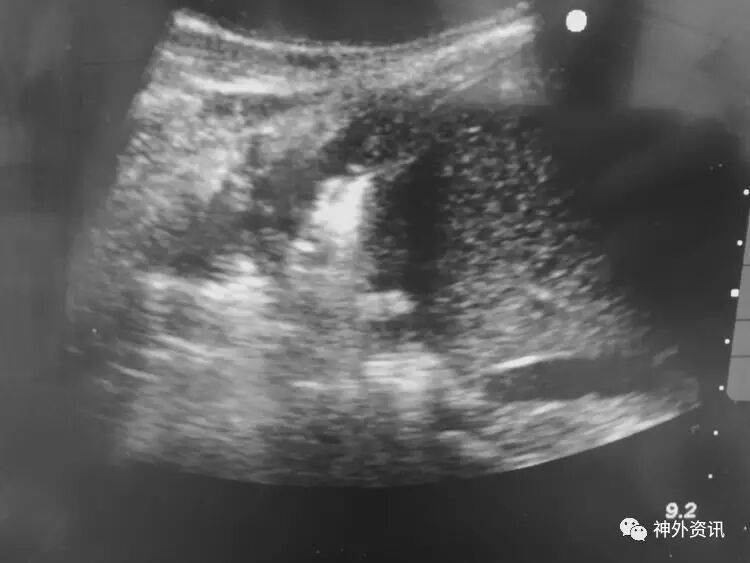

胸部CT及超声显示双肺底存在肺不张:

前胸超声:

肺底超声: